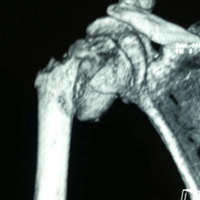

Case:2 Fracture of Neck Humerus with Fracture of Greater Tuberosity

Pre-Op AP

Pre-Op Trausaxillay